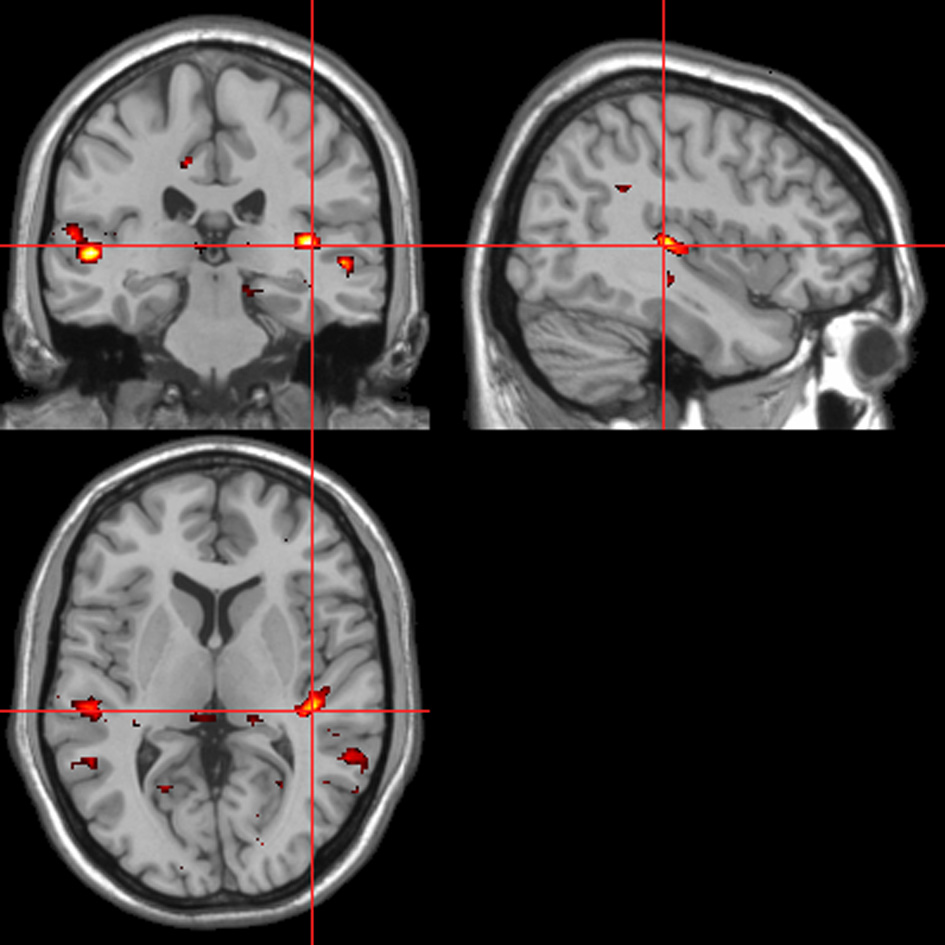

fMRI—autonomic (ISCR)-behavioral response convolved regressor

Across all stimuli, the interaction between autonomic (ISCR) and “threatening” or “harmless” assessment responses—our PAI was associated with activation of right MidFG (BA 10; T&T co-ordinates 24 42 −7) and left mid-cingulate gyrus (BA 24; −6 −23 36). Threatening picture-ISCR interactions were associated with activation of right fusiform gyrus/parahippocampal gyrus (BA 37; Table 3B and Figure 8). Threatening sentence-ISCR interactions were associated with activation of right insula and MidFG (BA 10), left thalamus [ventral posterolateral (VPL) nucleus], left superior temporal gyrus (BA 22) and left cerebellum (Table 4B and Figure 10). Threatening sound-ISCR interactions were associated with activations including left mid-cingulate gyrus, bilateral postcentral gyrus (BA 1/2/3), bilateral IFG (BA 44/47) and right inferior parietal lobule (BA 40; Table 5B and Figure 12). This left mid-cingulate gyrus activation survived FWE correction at p < 0.05.

Figure 11

Sounds. Activations associated with “threatening” compared with “harmless” behavioral responses. Flexible factorial design p < 0.001. Extent threshold = 10. See Table 5A for anatomical descriptions and co-ordinates.

Figure 12

Sounds. Psycho-autonomic interaction (PAI) between integrated skin conductance response (ISCR) and behavioral response (“threatening” > “harmless”). Flexible factorial design p < 0.001. Extent threshold = 10. See Table 5B for anatomical descriptions and co-ordinates.